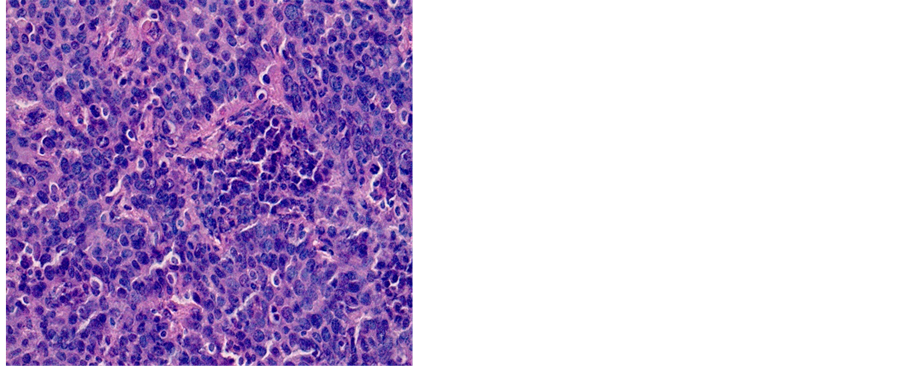

Table 2 shows the distribution of histological types of cancers diagnosed during the study. A total of 1687 (81.18%) cases of squamous cell carcinoma (SCC) and 269 (12.95%) cases of adenocarcinoma (ADK) have been identified (Figures 3-5).

Figure 4. Poorly differentiated SCC (a) 200×; (b) 400×.